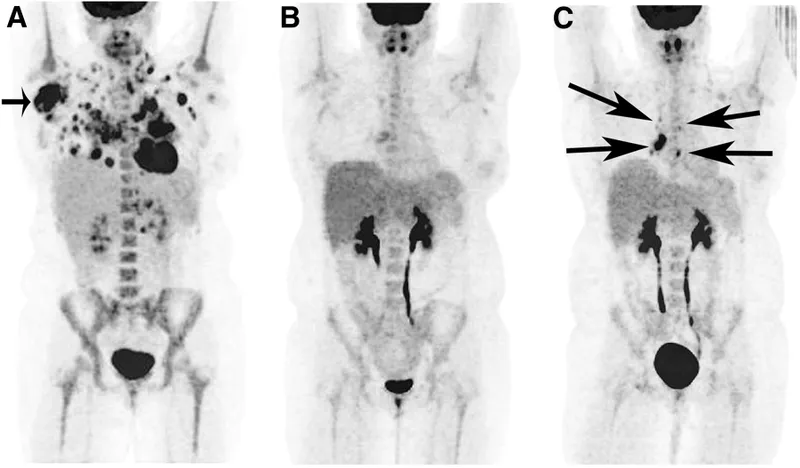

- PET-CT (Positron Emission Tomography): Uses $F^{18}$-FDG to map metabolic activity. Crucial for cancer staging, monitoring treatment response, and identifying viable myocardium.